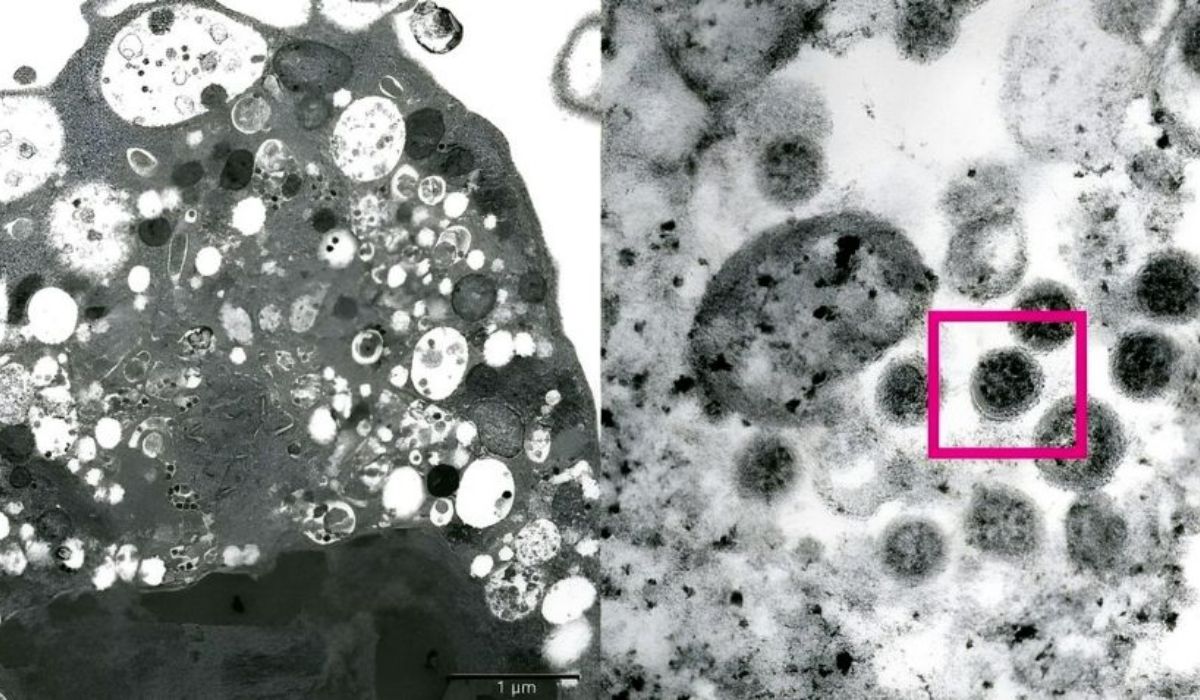

Mientras, algunos expertos han apodado a BA.2 el 'ómicron sigiloso' porque tiene rasgos genéticos que hacen más difícil identificarlo en las pruebas de PCR. Asimismo, la OMS publicó que, a diferencia de la subvariante predominante, BA.2 "no causa una marca concreta en las pruebas de laboratorio denominada 'fallo de objetivo del gen S', lo que hace que pueda parecerse a otras versiones del coronavirus, como la delta, en un primer cribado". No obstante, esto no significa que no se la pueda detectar, sino que se hace de forma distinta.